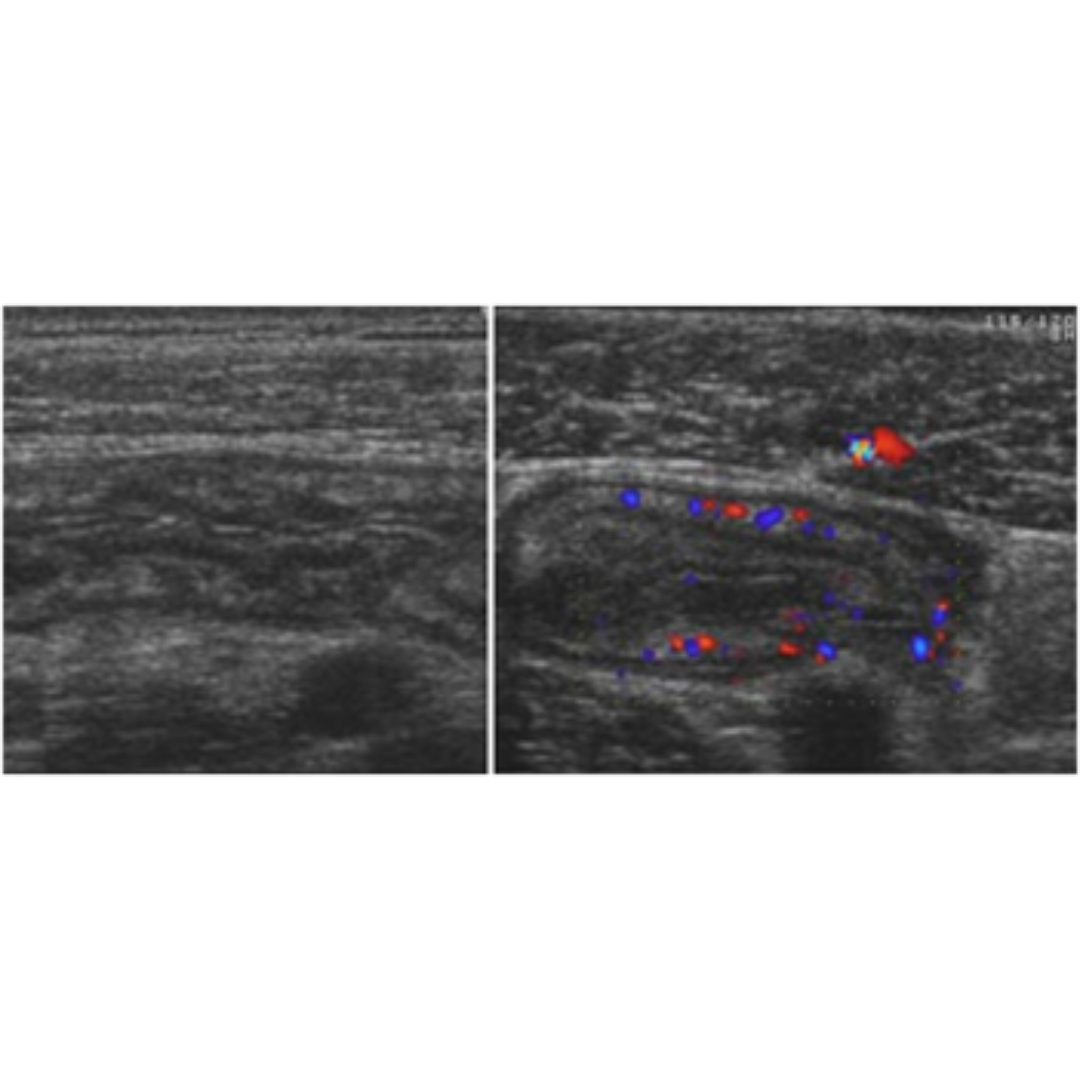

Signos US: pared intestinal engrosada (> 3 mm) y no compresible, capa submucosa engrosada e hiperecogénica, aumento de la ecogenicidad de la grasa adyacente, hiperemia parietal, disminución del peristaltismo, adenitis mesentérica(*).

Figura 2: Pared intestinal engrosada e hiperemia.

Es la inflamación de ganglios linfáticos del mesenterio, es considerado un signo en respuesta a inflamación y no un diagnóstico.

Signos US: aumento de tamaño de varios ganglios linfáticos (AP > 7 mm) presentes en FID y/o mesogastrio, con aumento de vascularización hiliar al Doppler color.

Figura 3: Múltiples ganglios aumentados de tamaño, se observa incremento de su vascularización hiliar.